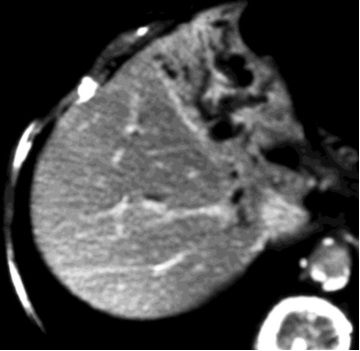

经皮定位穿刺是指经皮穿刺胆道前在皮肤标记进针穿刺点 经皮超声引导下引流 经皮CT引导下引流 经皮透视引导下引流

经皮定位穿刺是指经皮穿刺胆道前在皮肤标记进针穿刺点

经皮CT引导下引流

CT引导

穿刺点的选择包括皮肤穿刺点的选择和胆道进入点的选择